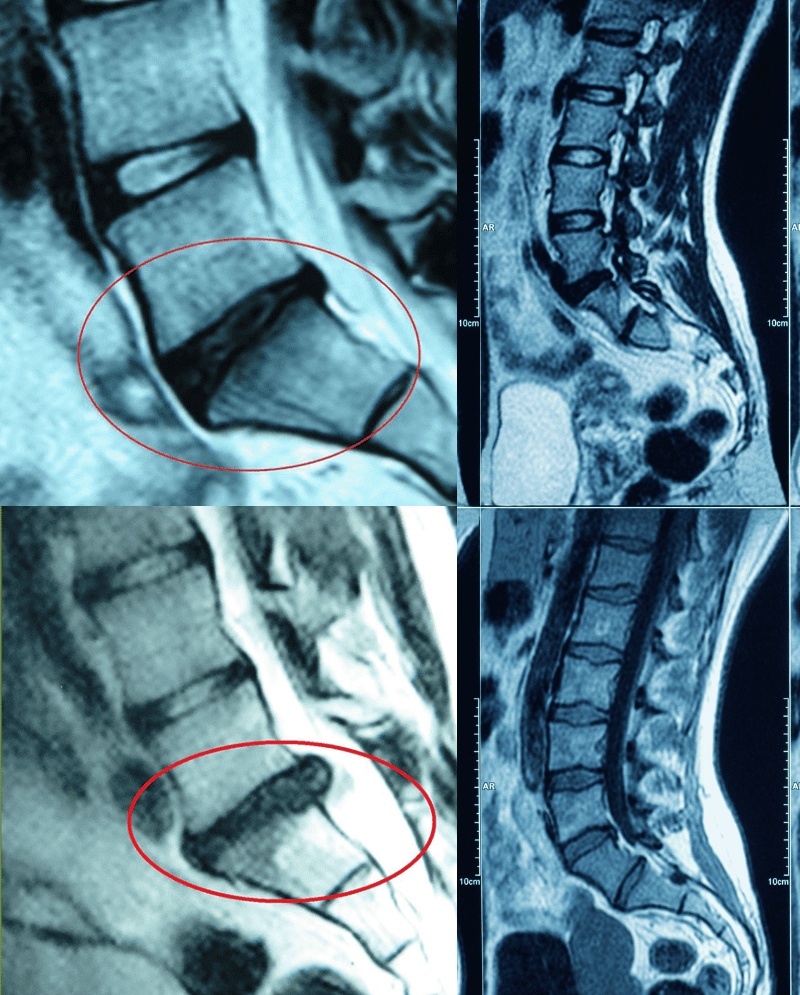

Conditions We Commonly Treat

*Herniated, Bulging, or Protruding Discs, * Degenerative Disc Disease, *Chronic Neck or Low Back Pain, *Sciatica, *Radiculopathy (radiating pain, numbness, tingling, or weakness into the arms/legs), *Facet Joint Irritation, *Arthritis-Related Spinal Stiffness, *Spinal Stenosis (in select cases)